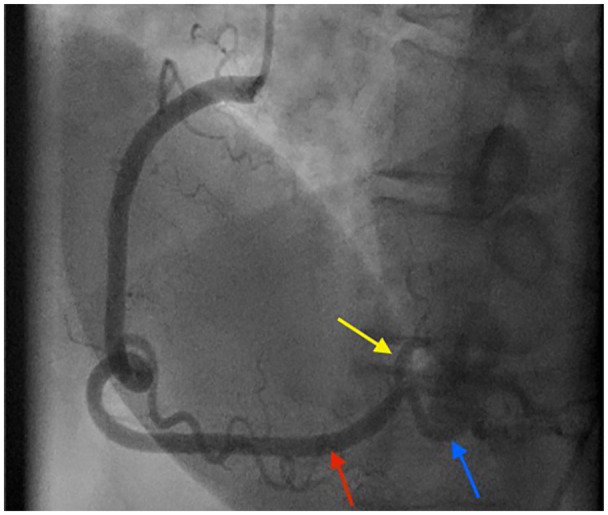

一名18岁的青少年患有明显的动脉粥样硬化性心血管疾病(ASCVD)危险因素,并发急性胸痛。他的心电图显示st段下位抬高。急诊冠状动脉造影显示右冠状动脉血栓性闭塞。他接受了罪魁祸首病变支架置入术,临床完全恢复,继发于心肌梗死的心电图异常也得到了解决。

An 18-year-old teenager with significant atherosclerotic cardiovascular disease (ASCVD) risk factors developed acute chest pain. His electrocardiogram showed inferior ST-segment elevations. Emergent coronary angiogram revealed complete thrombotic occlusion of the right coronary artery. He underwent stenting of the culprit lesion with complete clinical recovery and resolution of his electrocardiographic abnormalities secondary to myocardial infarction.